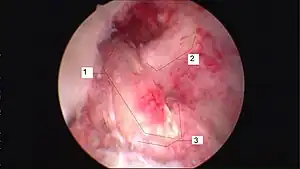

![]() | |

| Arthroscopic anterior cruciate ligament (ACL) reconstruction (right knee). The tendon of the semitendinosus muscle was prelevated, folded and used as an autograft (1). It appears through the remnant of the injured original ACL (3). The autograft then courses upwardly and backwardly in front of the posterior cruciate ligament (2). | |